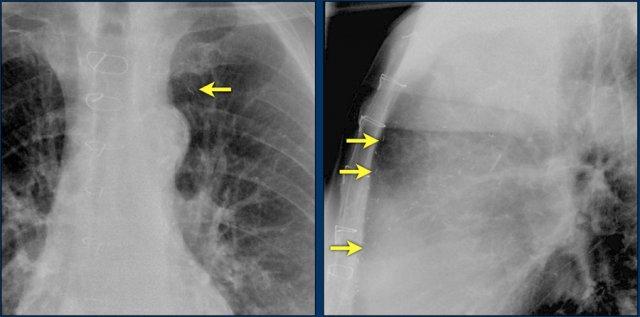

Hội chứng Twiddler

Hội chứng Twiddler là tình trạng máy tạo nhịp tim hoạt động không bình thường do bệnh nhân tự tác động vào thiết bị, dẫn đến lệch vị trí các điện cực.

Hậu quả là máy tạo nhịp hoạt động sai chức năng hoặc đôi khi kích thích các cấu trúc khác như thần kinh hoành hoặc đám rối thần kinh cánh tay.

Hình ảnh bên trái cho thấy bệnh nhân có ICD được đặt đúng vị trí.

Vài tháng sau, thiết bị hoạt động không bình thường do hộp ICD và điện cực bị xoay (mũi tên vàng) và co rút lại (mũi tên trắng).

Đây là một bệnh nhân khác mắc hội chứng Twiddler.

Lưu ý hình ảnh điện cực bị cuộn xoắn gần máy tạo nhịp và tại đầu điện cực trong thất phải (mũi tên).